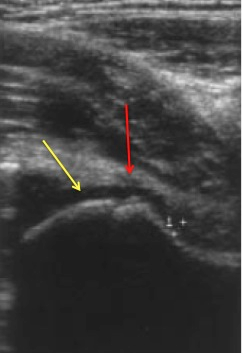

• Ultrasound

• indications

• neonate contralateral hip

• in neonates ultrasound both hips if any septic joint is found, signs and symptoms of infection are muted in neonates, and a missed infection can be catastrophic.

• can be used to guide aspiration

• findings

• may be helpful to identify effusion

• cannot differentiate between a septic and a sterile effusion